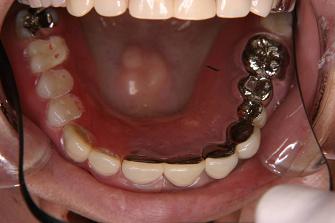

【症例 4】6歯欠損 (55才,女性)

正面上(ミラー像)

1.

術前のお口の状態です